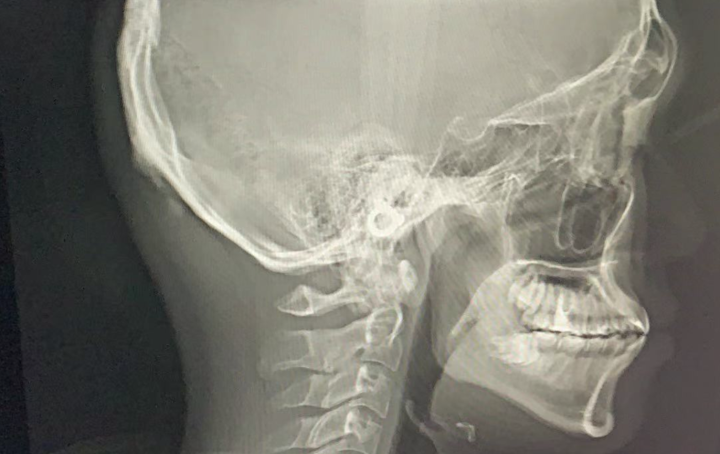

矫正前-------在做矫正前,需要先面诊,拍片子,出方案,收费如下:

面诊费用+一次性检查材料费用+拍x光片费用+口扫费用(或者取模型)+出方案费用。